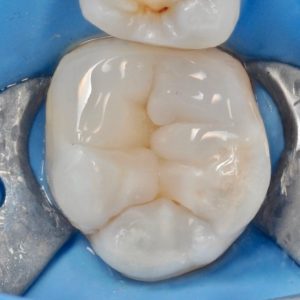

тщательная обработка каналов

Точное определение геометрии каналов и их качественная обработка

зуб с обработанными каналами